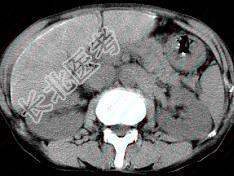

- 单项选择题男,40岁有血吸虫感染史,腹胀不适,食欲减退,CT扫描所见如图,最可能的诊断是 ( )

A、肝炎后肝硬化

B、血吸虫后肝硬化

C、酒精性肝硬化

D、胆汁性肝硬化

E、脂肪肝